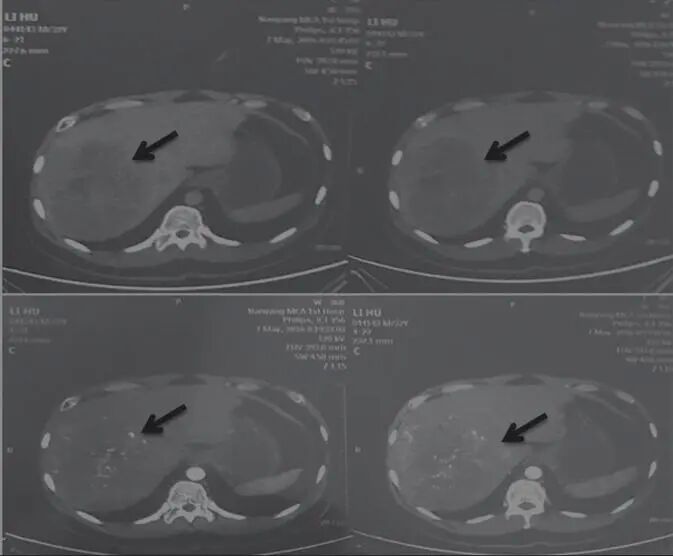

2017年11月1日,AFP 1027ng/mL查说明肿瘤并没有消失,但是病变部位有所减小(图2)。

图2 舒达少阳防治肿瘤验案2017年11月1日CT结果